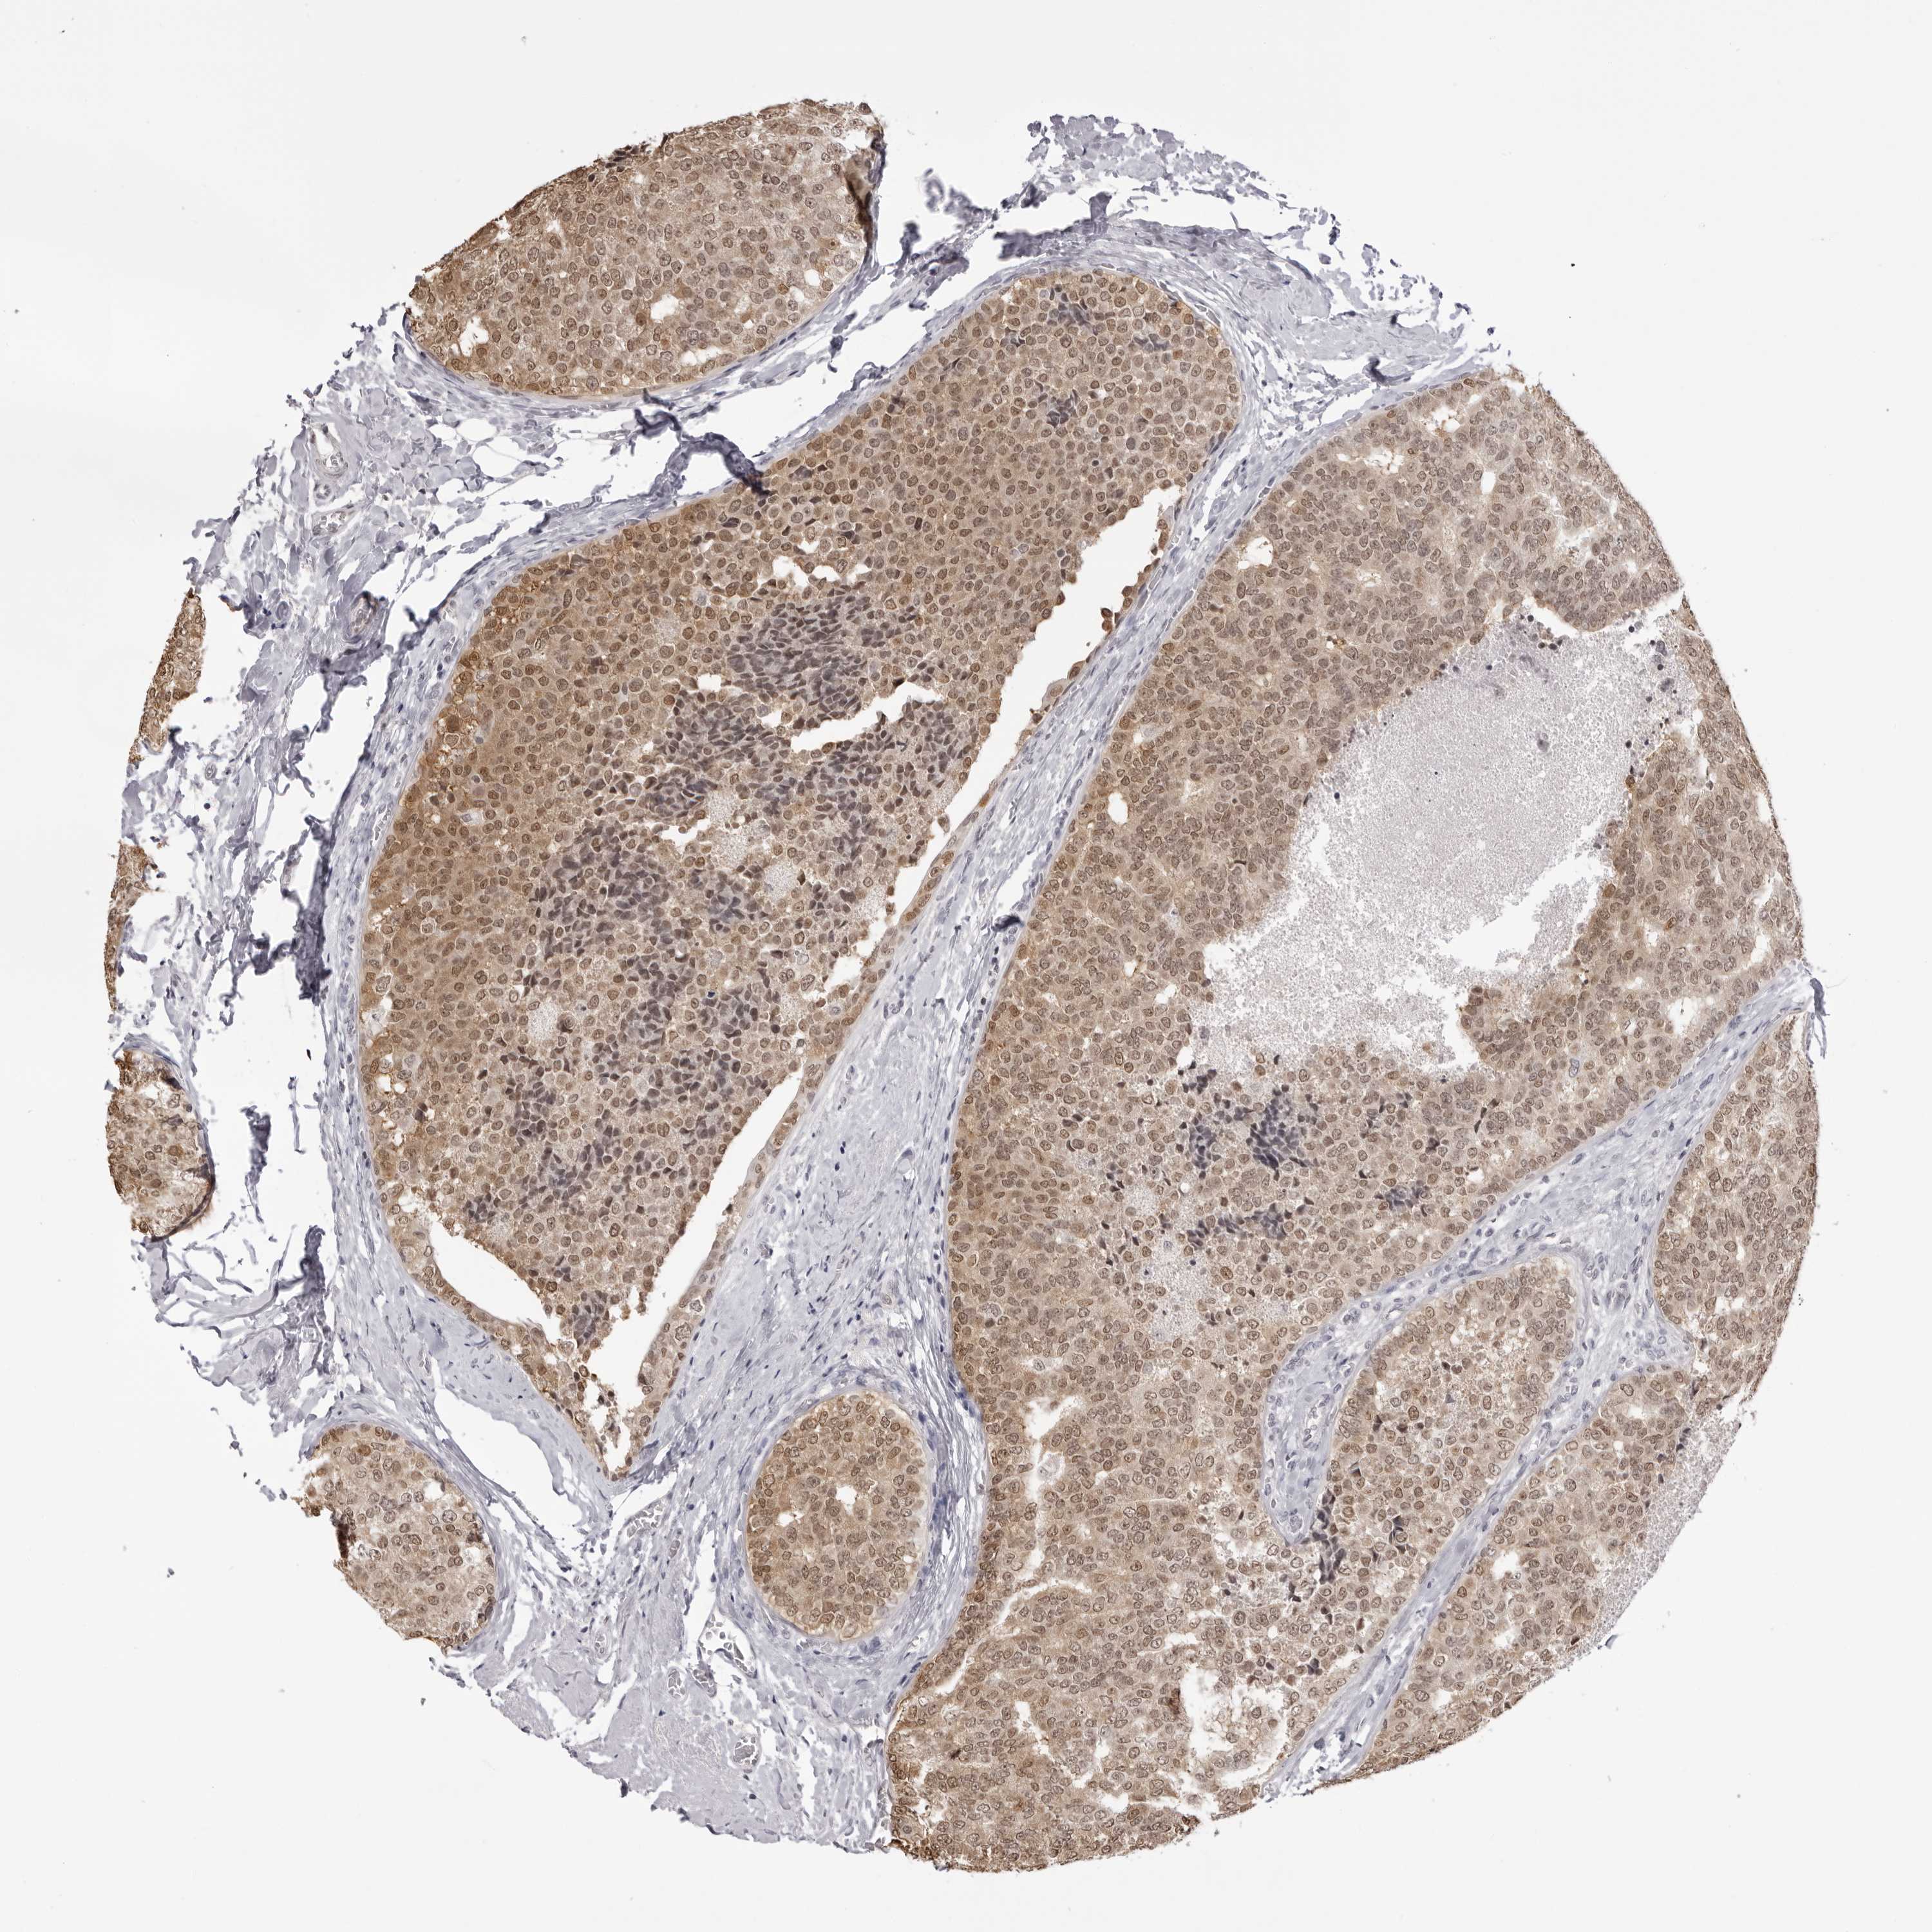

CANCER BREAST CANCER Show tissue menu

BRCA TCGA BRCA VALIDATION PROTEIN EXPRESSION